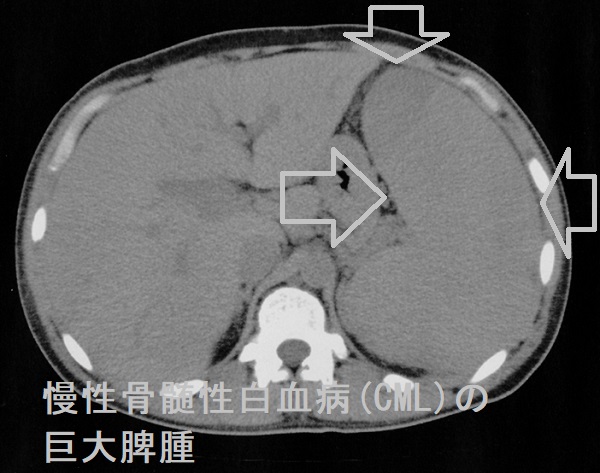

慢性骨髄性白血病 (CML) は、骨髄に影響を及ぼすがんの一種です。血液を形成する細胞から始まり、がん細胞が時間をかけてゆっくりと増殖していきます。病気の細胞は死ななければならないときに死なず、徐々に健康な細胞を追い出します。